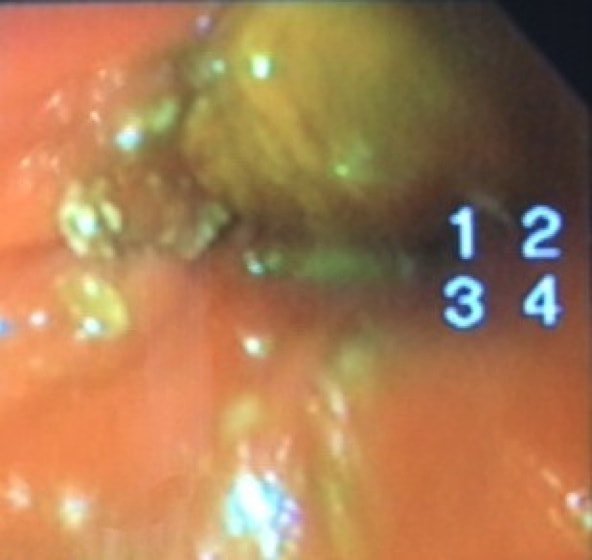

症例:炎症性ポリープ M.ダックス 10歳 オス

主訴:8ヶ月前から便が細くなり、血が混じることがある。その他、元気・食欲等、一般状態は良好。

経過:超音波検査にて直腸壁の肥厚(5㎜)が認められた。また、直腸検査で直腸全周に結節状病変を触知し、出血も確認された。消炎剤、抗生剤、整腸剤による治療への反応が長期的に悪いため、生検も含めた内視鏡検査を実施した。

内視鏡検査:肛門付近の直腸全周に、炎症および出血を伴う結節状病変を多数認めた。

病理検査:直腸の病変は、良性の非腫瘍性病変の一つである“炎症性ポリープ”と診断された。

診断後経過:炎症性ポリープは多発する傾向や腫瘍に転化する可能性があるため、消炎剤、抗生剤、整腸剤による内科療法を継続しながら、現在プルスルー法による外科的摘出術を検討中。

◎炎症性ポリープとは

近年、ミニチュアダックスで好発が知られている良性の腫瘍性の病変です。しばしば多発し、また腫瘍に転化する事があります。